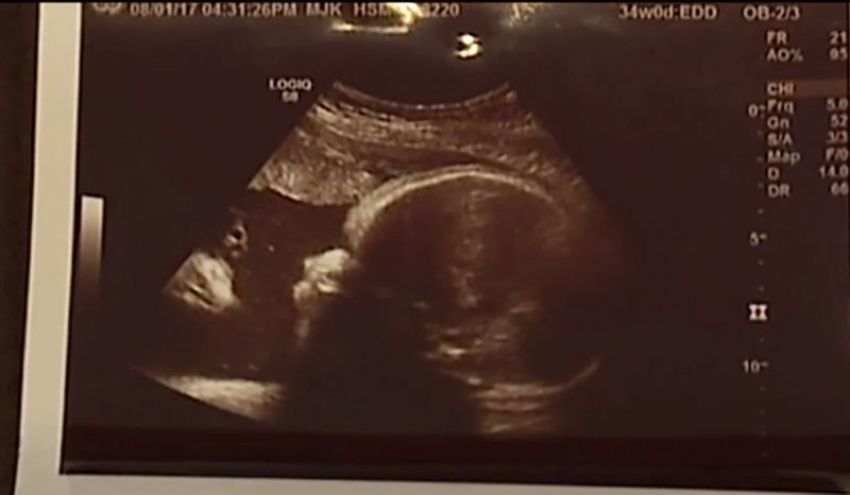

Sonogram Shows Jesus Watching Over Baby in Womb, Pennsylvania Couple Says

A Pennsylvania couple found an image of Jesus Christ watching over their unborn daughter in a sonogram.

"When they gave it to us ... Umm, to me, it's Jesus. And it looks like Jesus," the mother, Alicia Zeek, told WPMT on Tuesday, referring to the sonogram.

Zac Smith, the father, also said that the image is mystifying.

"This is distinct — I mean, there's another face looking at my daughter!" he claimed.